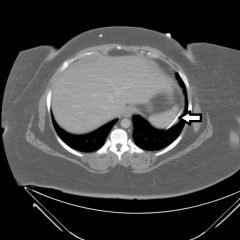

An 80-year-old female with a history of Crohn’s disease presented to the emergency department with chest pain. She had two weeks of exertional chest pain that preceded an episode of chest pain immediately prior to arrival associated with diaphoresis. Her pain nearly completely resolved with sublingual nitroglycerin provided by pre-hospital personnel. She was hemodynamically stable with normal vital signs on arrival. An ECG was immediately obtained.

The ECG shows ST-segment depressions in precordial leads V3 through V6, and limb leads I, II, and aVL, and 1 mm of ST-segment elevation in aVR. The initial troponin I was elevated at 1.37 ng/mL (upper limit of normal 0.40). Cardiology decided to delay catheterization until the next day when diffuse coronary disease was discovered (including 90% of the left circumflex stenosis, 60% proximal and 75% mid-left anterior descending stenosis, 75% third diagonal branch stenosis, and 90% posterior descending artery stenosis). The following day, the patient went to the operating room for coronary artery bypass grafting (CABG).

Traditionally, lead aVR has not received attention when interpreting acutely ischemic changes on ECG, leading some to refer to it as “the forgotten lead.”1 Current guidelines acknowledge the significance of multilead ST depression with coexistent ST elevation in aVR, and this pattern has been identified as the strongest predictor of severe left main coronary artery and/or 3-vessel disease.2-3 When this ECG pattern is recognized in patients with ischemic symptoms, the emergency physician should involve cardiology early.